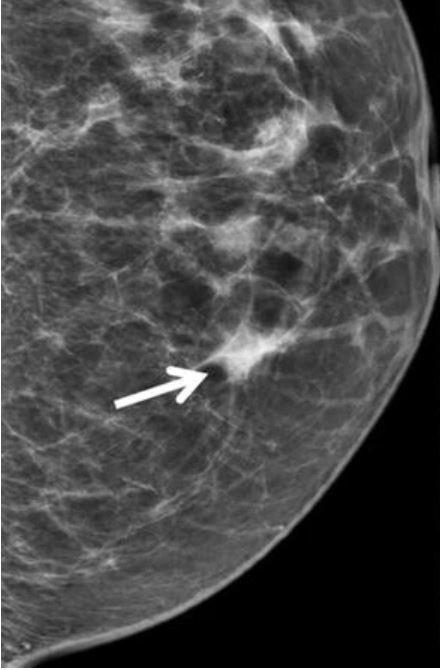

A mammogram showing a focal asymmetry in the breast.

Abnormal or uncertain results on mammograms (arrow) are common and may lead to additional testing to rule out cancer.

Credit: Current Radiology Reports. January 2018. https://doi.org/10.1007/s40134-018-0266-8. CC BY 4.0.